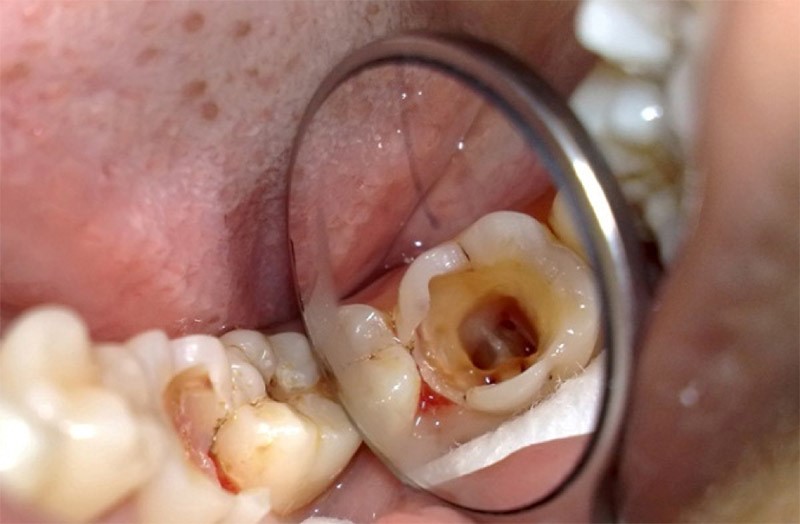

Nếu tủy viêm chưa được loại bỏ hết bác sĩ sẽ chỉ định chữa tủy lại kết hợp với vệ sinh ống tủy bằng các dung dịch sát khuẩn. Sau khi đảm bảo tủy viêm lấy hết bác sĩ sẽ tiến hành trám hoặc bọc sứ để khôi phục khả năng ăn nhai, cải thiện tính thẩm mỹ.

(Kết quả chữa tủy răng được thực hiện tại Peace Dentistry)(**)